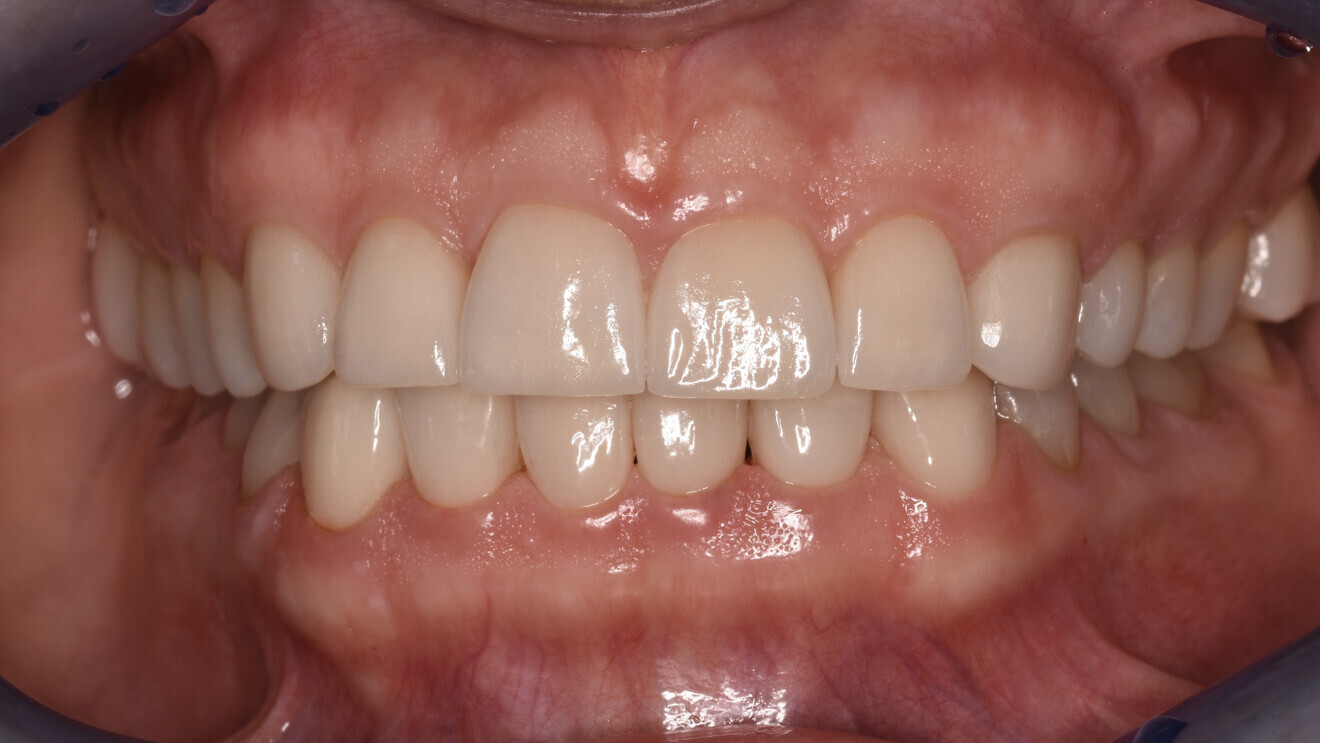

After a dripping time of 10 minutes, unpolymerised resin residue was removed from the printed objects using a brush soaked in isopropanol. The objects were then detached from the build plate, and the supporting structures were removed. Post-polymerisation was performed 15 minutes after the last isopropanol contact, using two cycles of 2,000 flashes each in the Otoflash G171 (NK Optik). After post-processing, the provisional restorations were finished and polished to a high gloss (Figs. 10a-g). Finally, the temporary luting was completed with a dual-polymerising temporary luting composite (Bifix Temp, VOCO; Figs. 11a-e).

After the provisional restorations had been worn for six months, the newly defined occlusal relationship was transferred to final restorations. Adhesively fixed restorations made of monolithic lithium disilicate (IPS e.max Press, Ivoclar) were the first choice (Figs. 12 & 13). Owing to the thin margins in some areas, it was preferable for the restorations to be fabricated using the press technique.

Fig. 13: Final lithium disilicate restorations.